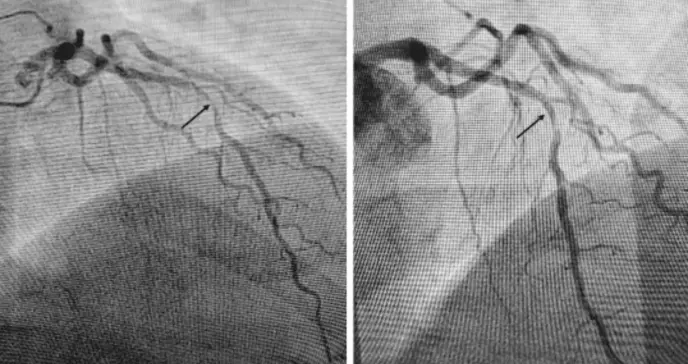

El paciente fue trasladado para cateterismo cardíaco urgente, donde se identificó una lesión crítica en la arteria descendente anterior (DAI), conocida coloquialmente como "la arteria asesina". Se realizó angioplastia con colocación de stent, logrando la revascularización exitosa del territorio afectado.